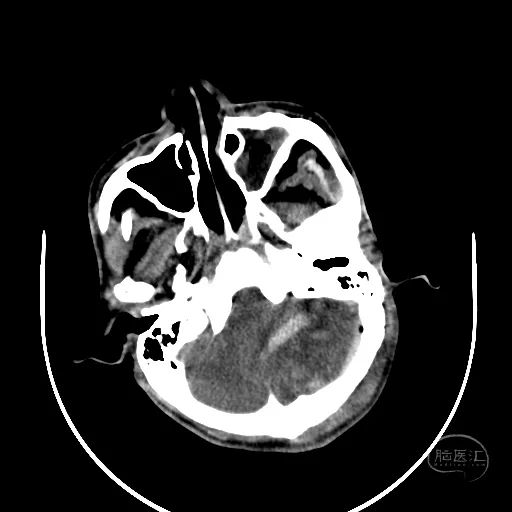

2小时后复查颅脑CT显示第四脑室受压消失。

小脑挫伤灶水肿较前加重,脑干及小脑半球低密度改变。

硬膜外血肿无明显变化。

右额叶脑挫裂伤并脑内血肿形成,中线结构明显移位。

左侧脑室有扩张表现。

此时患者双侧瞳孔散大,GCS评分4分,气管插管,自主呼吸。家属同意手术治疗。

幕上脑疝,幕下压力也高,第四脑室闭塞,导水管显示不清,脑室有扩张表现。